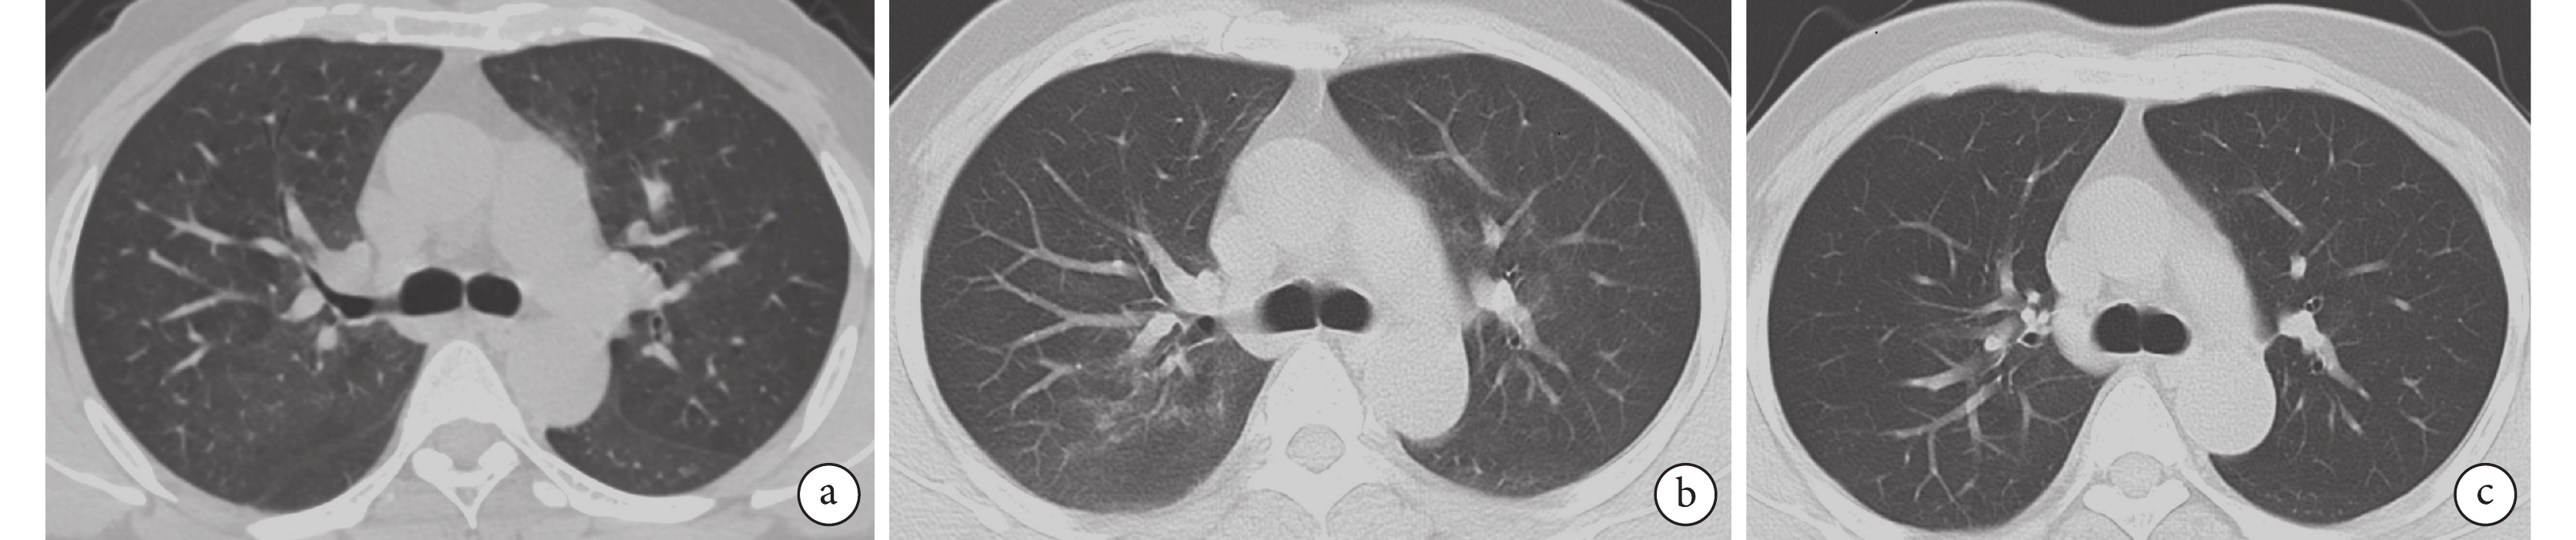

患者 1 于 2022 年 6 月 12 日入院,胸部 CT 示“雙肺多發斑片狀磨玻璃密度影:病毒性肺炎?”(圖1a),入院后先給予莫西沙星 4 d,病情無改善;2022 年 6 月 17 日復查胸部 CT 示雙肺滲出影大致同前(圖1b),BALF-mNGS 檢出 TW、肺炎鏈球菌、流感嗜血桿菌,改用美羅培南聯合多西環素治療 7 d;2022 年 6 月 24 日復查胸部 CT 示雙肺滲出影較前明顯吸收(圖1c)。患者于 2022 年 6 月 25 日病情好轉出院。

a. 雙肺紋理增粗,可見多發斑片狀磨玻璃密度影,以外周帶分布為主;b. 予莫西沙星治療 4 d 后,雙肺滲出性病變大致同前;c. 予美羅培南聯合多西環素治療 7 d 后,雙肺滲出性病變較前明顯吸收